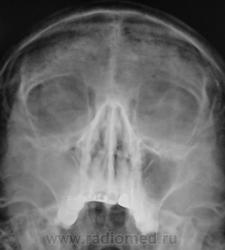

С двух сторон  отсутствие лобных пазух, встречается это нечасто... И правоторонее субтотальное затемнение гайморовой пазухи. Травматических изменений не обнаружил.

Двухсторонняя аплазия лобных пазух. Правосторонний верхнечелюстной синусит. Вероятно, блок соустья правой верхнечелюстной пазухи с наличием жидкостного отделяемого в ней. Левая верхнечелюстная пазуха не изменена.

.В просвете левой верх. чел пазухи минимальное количество жидкости( если снимок выполнен в вертикальном положении).

Видимо, Вы имеете в виду соустье гайморовой пазухи с полостью носа. Альвелярная бухта левой гайморовой пазухи имеет менискообразный уровень вязкого эксудата.

Именно так соустье верхнечелюстной (гайморовой) пазухи с полостью носа, но только не левой, а правой.